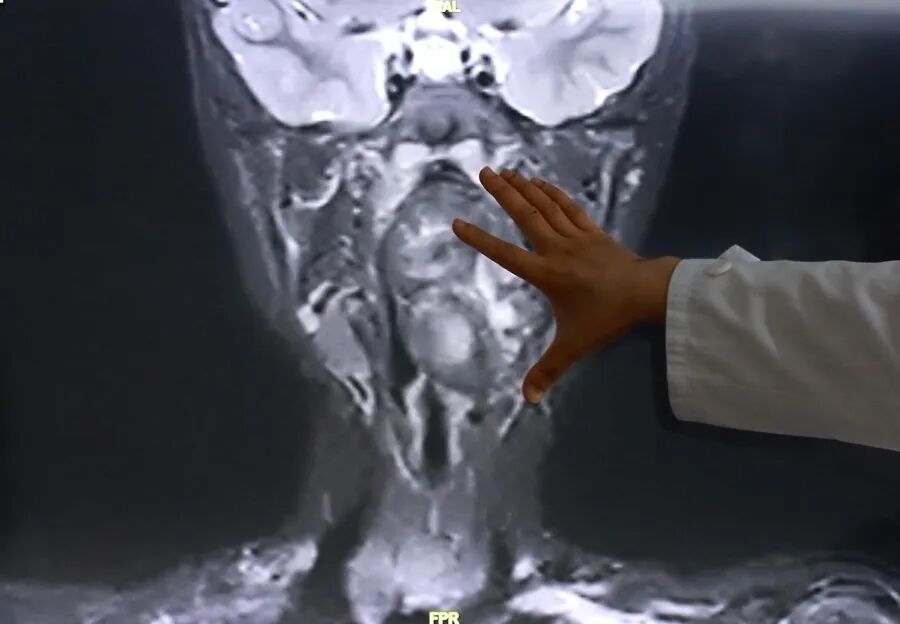

接诊后,综合前期检查及患儿家长自述病情,复旦儿科专家团队高度重视气道梗阻风险,立即启动复杂气道疾病绿色通道,完善增强CT及磁共振检查,明确小亮所患的肿瘤约7×3.5×3厘米,犹如“拳头”般大小。

专家表示,该肿瘤紧邻颈内动静脉并将血管明显向外推移,肿瘤向咽喉腔内隆起,占据大部分口咽及下咽腔,严重压迫声门,随时可能发生窒息。

陈超还表示,“6岁男孩的口咽腔大概在8公分左右,这个孩子的肿瘤已经高达6公分多,整个气道已经完全被这个膨大的肿瘤占据了,只有一条黑颜色的线,这是它透气的空间,再让它继续膨胀下来,它首先出现的一个症状应该是呼吸道的梗阻窒息,会出现窒息致死的可能。”